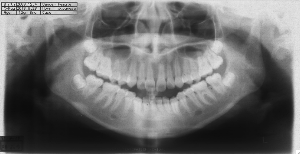

ステップ3. レントゲン(パノラマ、セファロ)撮影・口腔内写真撮影